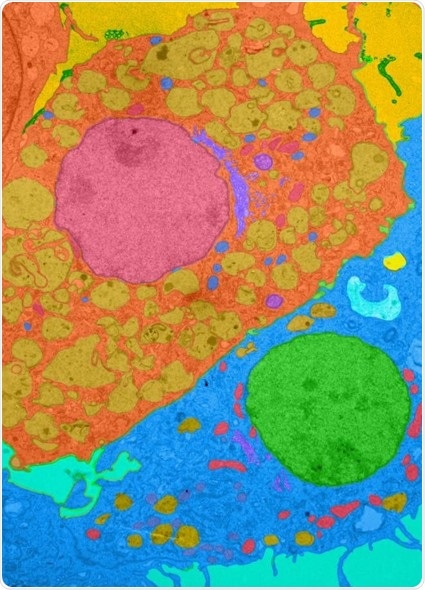

Colorized photomicrograph showing a macrophage (orange cell with large red nucleus in center of image) interacting with a fibroblast (blue cell with green nucleus at bottom right) in a mouse heart. Johns Hopkins Medicine researchers have shown that a protein, interleukin 17-A, can prevent critical monocyte cells from differentiating into lymphocytes that protect cardiac muscle from inflammation and in turn, lessen the threat of heart failure. Credit: X. Hou and D. Cihakova, Department of Pathology, Johns Hopkins University School of Medicine